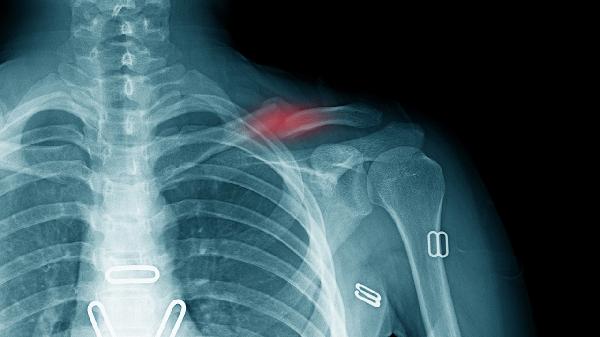

1、骨折诊断

X线是骨折诊断的首选影像学检查方法,能够清晰显示骨折线的位置、类型和移位程度。对于四肢长骨、脊柱和骨盆等部位的骨折具有较高敏感性,可帮助医生判断是否需要复位或手术干预。急性创伤后通常建议优先进行X线检查。